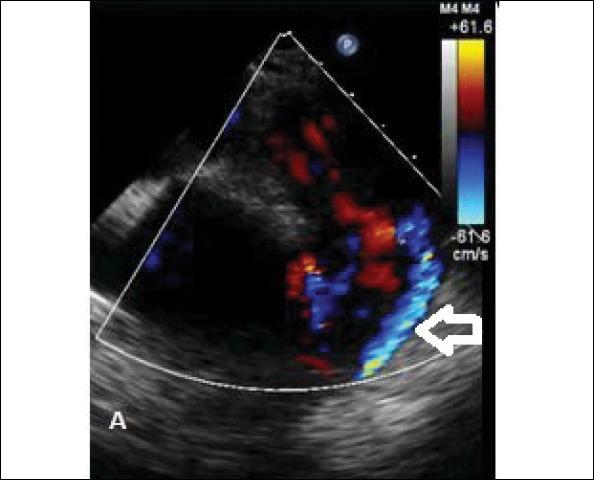

Papillary fibroelastoma associated with congenital heart disease: a coincidental association or a potential new syndrome?

Anatol J Cardiol. 2015 Nov;15(11):951-2. doi: 10.5152/AnatolJCardiol.2015.6371.